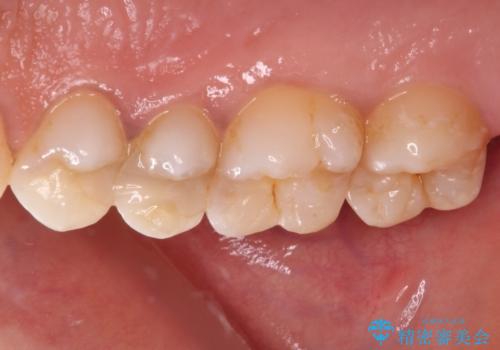

奥歯のむし歯をゴールドインレーで修復

- 奥歯にフロスが引っかかるようになり、虫歯ではないかとのことで来院された患者様です。

レントゲン写真より、左右奥歯にむし歯があることが分かりました。

奥で目立たないことから、虫歯の再発リスクが最も低く、咬合力による歯への負担も少ないゴールドインレー(PGAインレー、白金加金インレー)にて修復治療をすることとしました。

ゴールドインレーは銀歯のインレーやセラミックインレーと比べ、「技工操作の精度が高く、適合が著しく良い」というメリットがあります。特に上の奥歯は歯科医師の操作が行いにくいため、「適合の良さ」は再治療のリスクを防ぐ上でとても重要な要素となります。

上の奥歯は金属色が見えることもないため、審美的な問題は全くありません。

咬み心地はとても良好で、全く違和感がなく、患者様には大変満足していただきました。